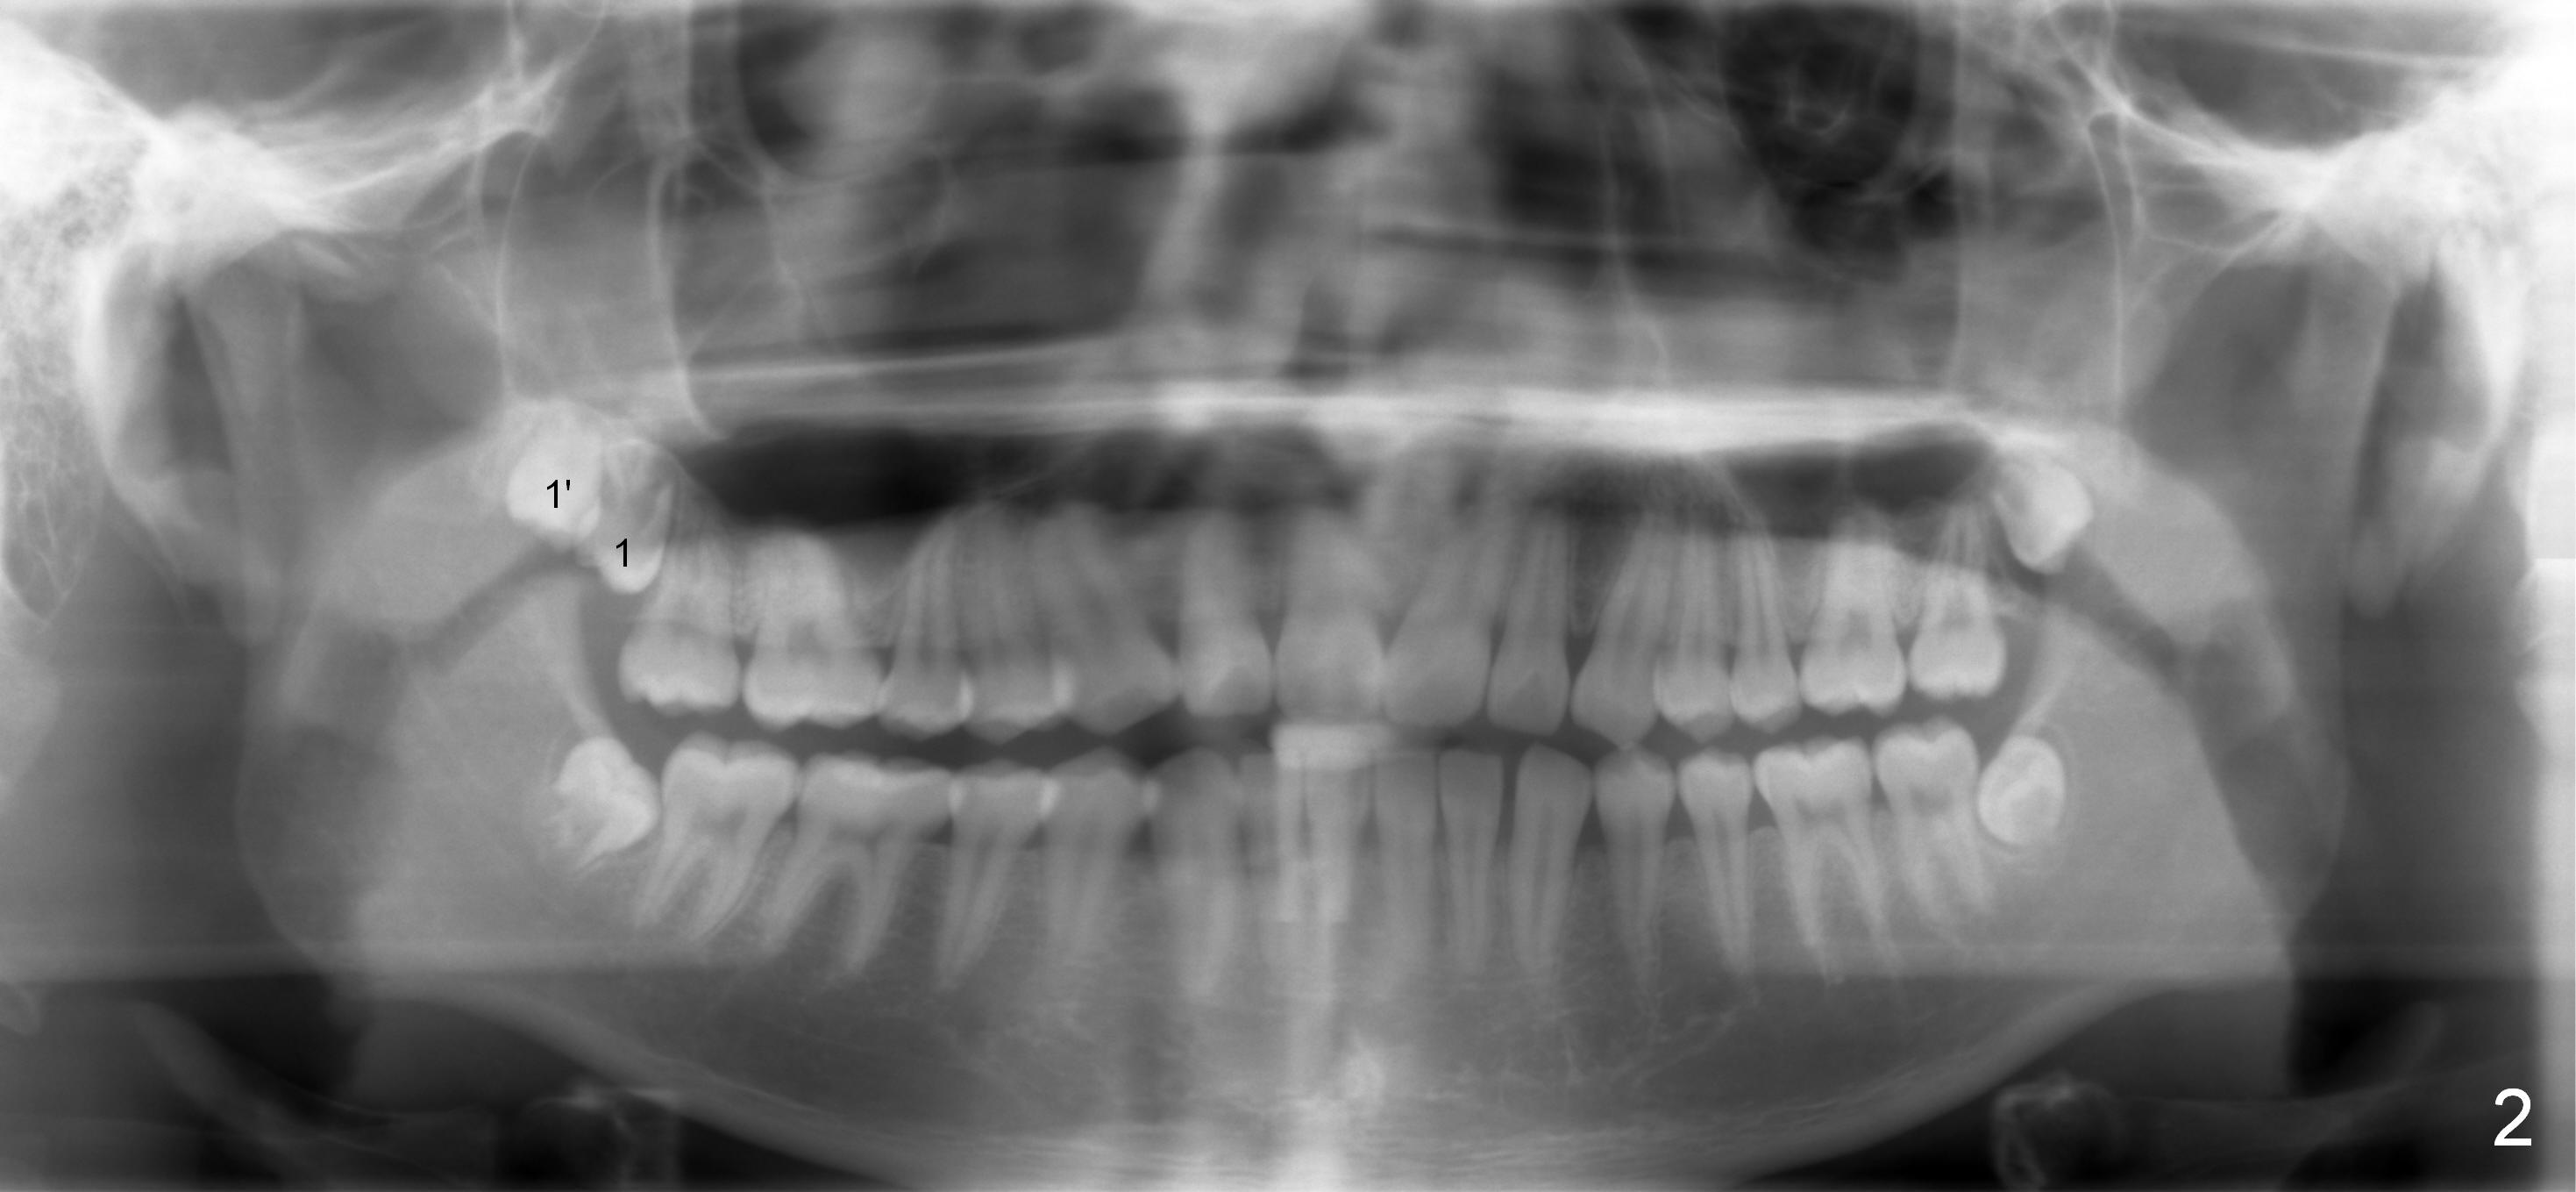

A 18 year old man has fully developing jaws.  It appears that there is enough room for 4 3rd molars to erupt normally.  In fact, the teeth #16,17,32 erupt.  Attached are pan taken 2 and 5 years ago (Fig.2,1, respectively).  I wonder whether we can take out one of the upper right 3rd molars and let the other erupt.  If the latter does not happen, #1 and 32 will be extracted.  The teeth #16 and 17 are not to be extracted.  Due to insurance limitation, the pan is not updated.  Thanks.

Now regarding this case.  No surgeon will take out wisdom teeth in a growing patient, which he is (the teeth anyway), without a current panx. So you are diagnosing from a weak position.  Regardless, you can see he has two #1 teeth--supernumerary.  It is clear the lower molars are mesial angularly impacted, with no hope of full eruption.  The upper wisdom teeth are still positioned high above the CEJ of the second molars, making removal difficult and traumatic.  But this is an old X-ray and we cannot make judgments because we know the roots are longer and the upper teeth have probably migrated more coronally.

The 18 year old is a boy, whereas the 29 year old is a lady.  The former needs extraction; the latter ortho.  I love your wood vision, particularly the relationship between Le Fort I and sleep apnea.  I did think of Le Fort I initially.  I am afraid that it may be the last resort, if there is such a need.  Look at Fig.1',2'.

Panoramic X-ray is taken immediately post extraction of one of the upper right 3rd molars (Fig.3,3') and 20 months postop (Fi.4,4').  In fact the remaining one has erupted normally.